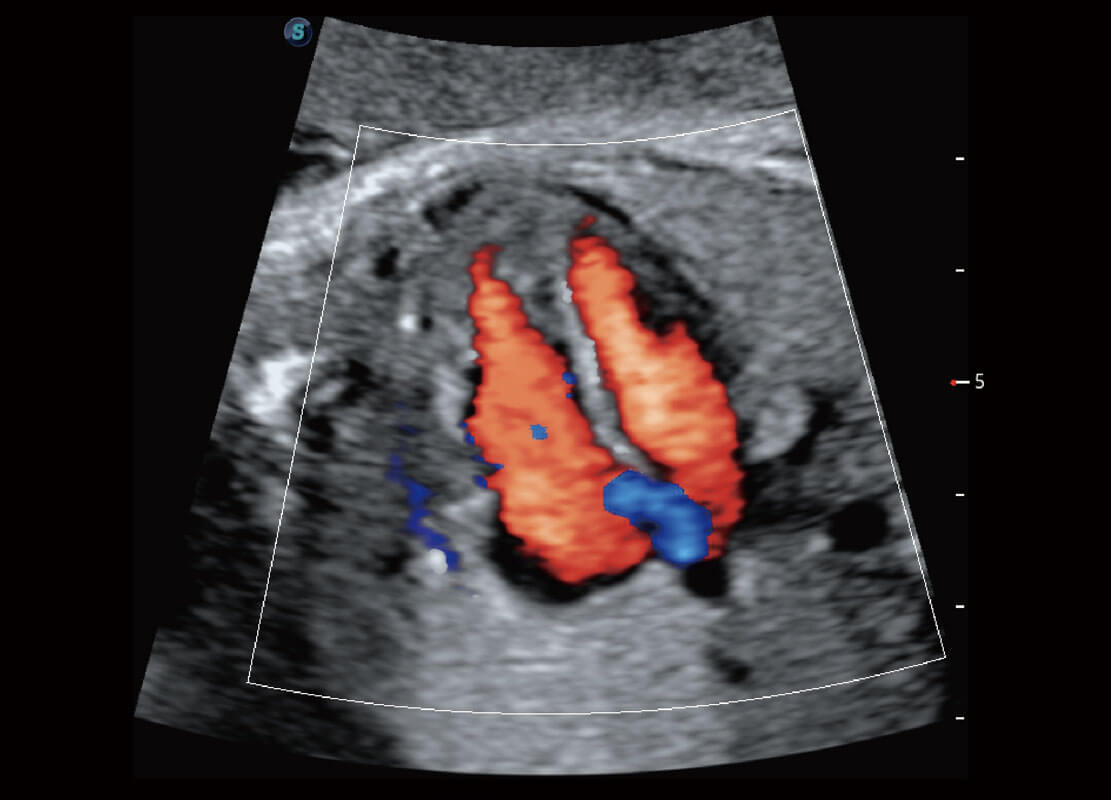

P60搭载一系列胎儿心脏成像技术,实现精细的胎儿心脏评估。

四腔心血流